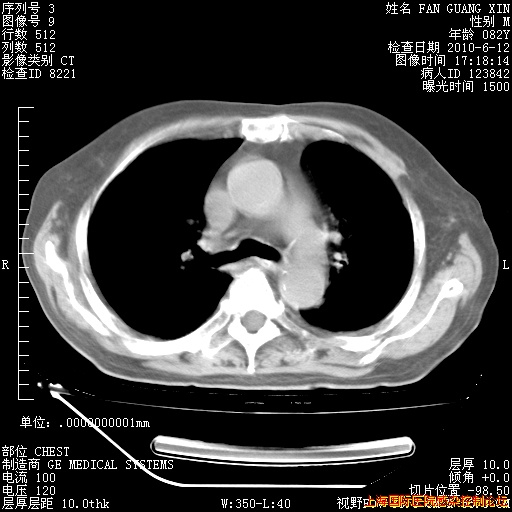

6月12日纵膈窗

6月10日改甲强龙80mg qd ,在南京年会期间体温不稳,18日有一次寒战后体温达39度。19日开始用甲强龙60mg bid ,加量后第二天就不发热。本打算在两周后即7月3日减量,但是7月2日洗澡受凉、发热、咳嗽、鼻音,口服复方大青叶片,甲强龙120mg用到9日(整整20天)。

自昨天起甲强龙改为80mg qd。

在抗结核治疗2周后一般情况逐渐好转。

整整相隔30天的肺部CT好像有所好转啊。甲强龙减量第3天,需要观察体温。

海管,自昨日你和我通完话后,不知您岳父消化道症状有无缓解?体温怎样?阅读7.12日胸部ct,个人认为目前激素治疗是有效的,甲强龙减量是适宜的。因在抗痨治疗,需密切观察肝功、肾功能和血常规。不过,老年、长期住院和大量使用激素,很担心菌群失调发生